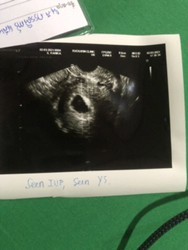

🥳เห็นน้องแล้วค่ะ ตอน9w1d แต่ก่อนหน้านั้นไปซาวตอน 4wเห็นแต่ถุง 5wก้ยังเห็นแต่ถุง 6wก้ยังเห็นแต่ถุง เริ่มเครียดค่ะ กลัวท้องลม แต่หมอก็นัดอีกทีตอน9w วันนี้เห็นแล้วค่ะ ดีใจมากๆๆ อยากจะเป็นกำลังใจให้แม่ๆที่ยังไม่เห็นนะคะ อย่าเครียดไปค่ะ เดี๋ยวก็ได้เจอตัวเล็กนะคะ 😘